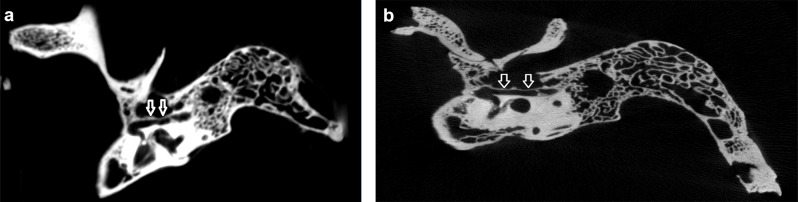

Results: Facial canal dehiscence was detected in 10 bones on micro-CT images, while 26 bones appeared intact. In contrast, CBCT images showed dehiscence in 25 bones, with 11 bones intact. Additionally, the mean dehiscence width was 3.469 mm (range: 1.577-8.921 mm) in micro-CT images, compared to 1.279 mm (range: 0.670-9.354 mm) in CBCT images. In the 10 bones where dehiscence was identified by both methods, the average width of the dehiscence measured 5.347 mm (range: 1.840-9.354 mm) in the CBCT images. The difference in measurements between CBCT and micro-CT was statistically significant (p < 0.05).

Conclusions and significance: The low resolution of CBCT was insufficient for visualizing the thin bony tissue lining the facial canal. These findings suggest that the frequency of facial canal dehiscence measured in preoperative CBCT images may be overestimated compared to actual anatomical conditions. These findings provide critical insights for preoperative evaluation and surgical planning in middle ear procedures.